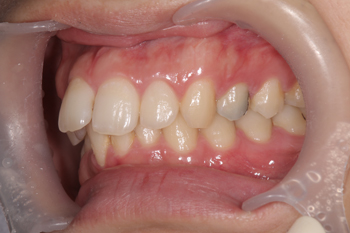

口ゴボ(上顎前突)と叢生の矯正相談

叢生と前突の方のマルチブラケットによる歯列矯正

歯並び矯正相談を希望されてご来院されました。歯に鈍痛が続いていて、前医では歯並びが原因と言われ、矯正を考え始めたそうです。他の矯正歯科にもご相談に行かれたそうですが、当院での治療をご希望されました。

Before

歯並びの状態としては、上の歯は前に出ている「前突」という状態で、下顎はガタガタに並んだ叢生という状態です。お痛みがあったため、矯正治療開始までに3ヶ月を要しましたが、無理にブラケットを着けると歯周病やむし歯が進行するため予め治療を行う必要があります。前医のご指摘どおり歯のお痛みは歯並びが原因で、咬合痛(咬み合わせの痛み)や清掃不全によるむし歯・歯周病等により、痛みが出ることは少なくありません。

3年弱で前突もなくなり、下の歯もきちんと並びました。

After

歯並びが整ったとはいえ歯周病やむし歯になるリスクはゼロではありません。今後も検診に定期的にてサポートさせていただきます。

治療の内容 マルチブラケット(クリア)による歯列矯正

期間・回数 3年2ヶ月・32回(カウンセリング・検査含む)

費用 自由診療:マルチブラケット(クリア) 総額 840,000円(税込924,000円)(調整料28回分含む)